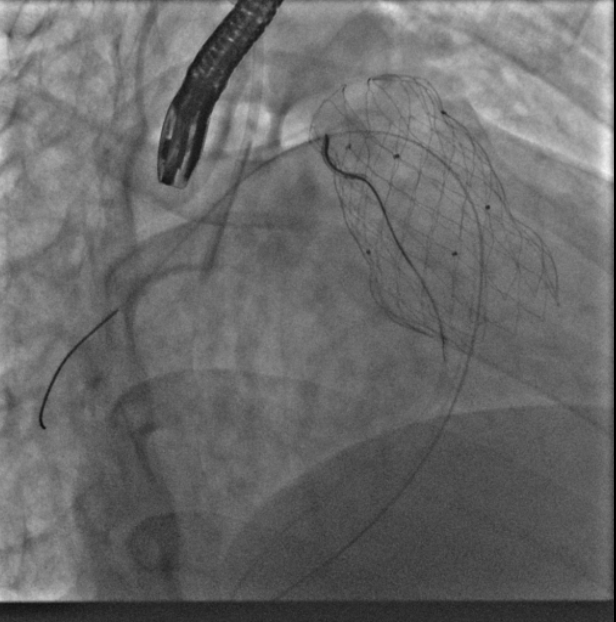

葛院士团队评估后认为,患者右肺动脉因阻挡存在狭窄,且右肺动脉与主肺动脉压差较大,具有临床意义,存在解决的必要。先后尝试Snare圈套瓣架下缘下拉法、双导管圈套瓣架上缘下拉法,但效果不理想,复测右肺动脉与主肺动脉压差仍较大,选择性右肺动脉造影仍存在右肺动脉狭窄。但考虑到患者利益,在安全操作的基础上,团队仍未放弃。拟通过将球囊送至右肺动脉开口处扩张,达到下压瓣膜支架、解除右肺动脉狭窄的效果,考虑到该操作的难点在于球囊无法顺畅到达肺瓣上目标位置,决定采用简略版PASS技术,即通过辅路送Snare至右肺动脉开口,并利用该Snare圈套住主路的Lunder quist导丝,换言之,即通过Lunder quist导丝两头发力将三尖瓣-右室流出道-右肺动脉这一扭曲的途径直线化且增强Lunder quist导丝支撑力,同时,由于Lunder quist导丝在右肺动脉处有附着力,可以避免瓣膜下移过多,如此球囊顺利通过瓣膜支架网孔进入右肺动脉,在DSA指引下逐步扩张球囊,成功使人工瓣膜支架向右心室侧移位。复查造影提示右肺动脉开口未见明显阻挡(图五),复测主肺动脉、左肺动脉、右肺动脉压力分别为32/9/19mmHg、32/7/18mmHg、29/7/17mmHg。复查肺动脉主干造影,显示人工瓣膜启闭良好,轻微瓣膜反流。最终手术疗效显著、取得令人满意的结果。

图五:通过PASS技术将球囊送至右肺动脉开口并扩张球囊、完成肺动脉瓣膜支架向心室侧移位,复查造影右肺动脉未见明显阻挡